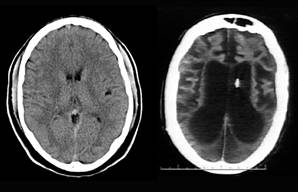

Врачи со стороны родителей заключили, что Терри находится в «состоянии минимального сознания», однако трое других экспертов, включая нейролога Рональда Кранфорда, подтвердили диагноз «необратимое вегетативное состояние».

Суд встал на сторону большинства экспертов, признав ее состояние безнадежным. Судья Джордж Грир, ведущий это дело, неоднократно выносил решения в пользу Майкла Шайво. А 18 марта 2005 года питание Терри было окончательно прекращено.